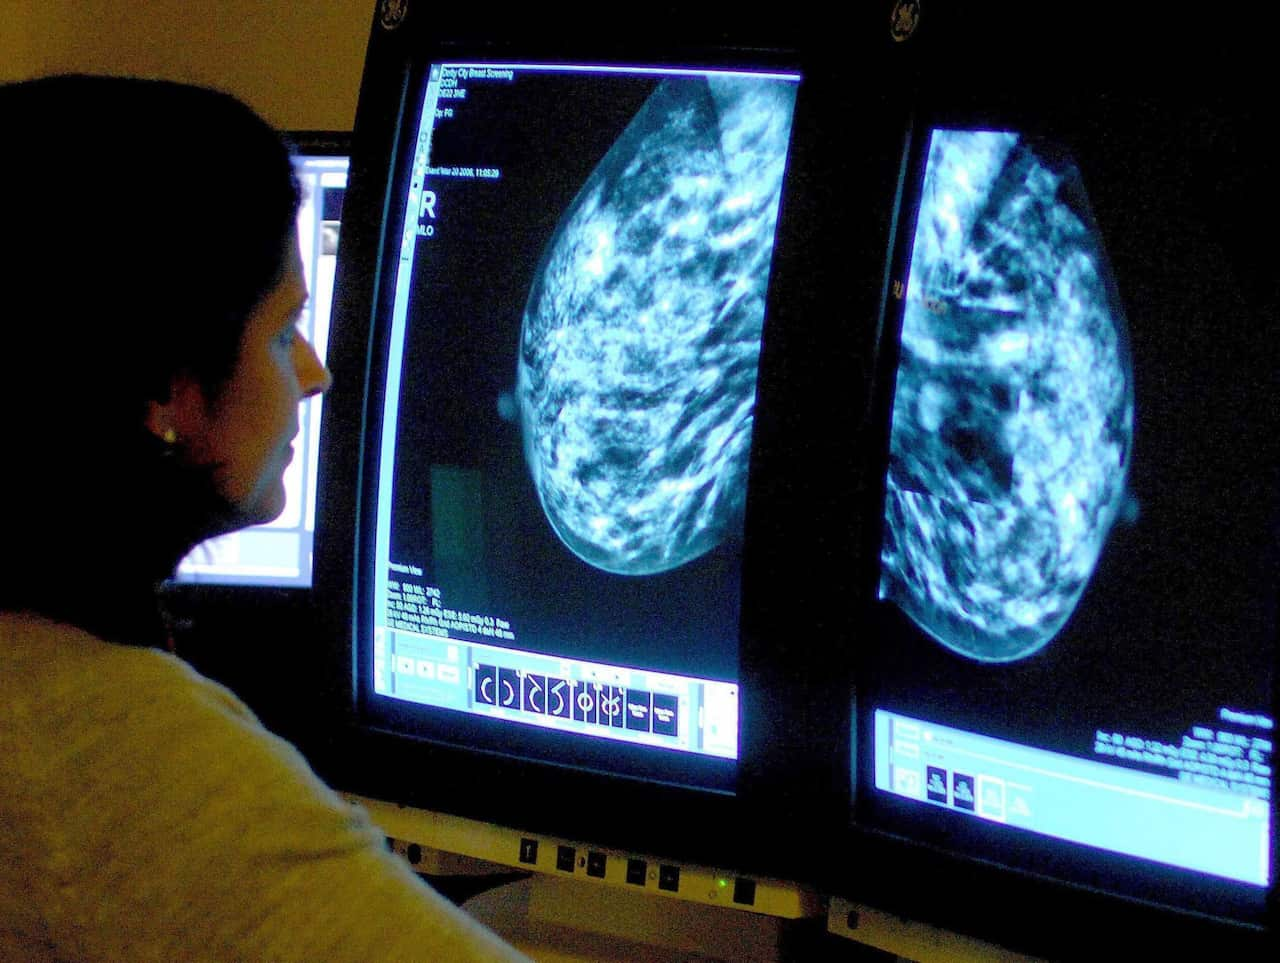

अनुसन्धान अगाडी बढ्दै जाँदा, डा थोमसले लि फ्राउमेनी सिनड्रोम भनिने विशेष किसिमका सूचक भएका मानिसहरूलाई टाउको देखि खुट्टा सम्म विशेष किसिमको एक्स रे, एमआरआई गर्न थाले।

एमआरआईबाट पत्ता लाग्ने भएपछि, धेरै मानिसले फाइदा लिन सकुन् भन्ने उद्देश्यले यसलाई बिस्तार गरिँदै छ।

डाक्टर थोमसले जेनेटीक मार्कर भएका यस्ता मानिसहरूलाई वार्षिक रूपमा एमआरआई गर्नका लागि मेडीकेयर समक्ष प्रस्ताव राखेका छन्।